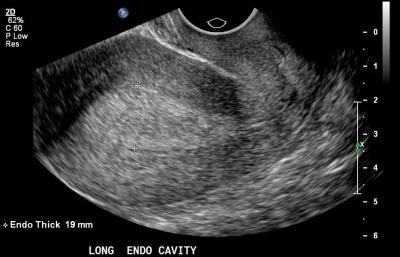

- трансвагинальное УЗИ;

Перечисленные процедуры позволяют врачам оценить состояние эндометрия: его толщину, особенности строения клеток, локализацию очагов гиперплазии. На основании полученных данных гинеколог разрабатывает тактику лечения.